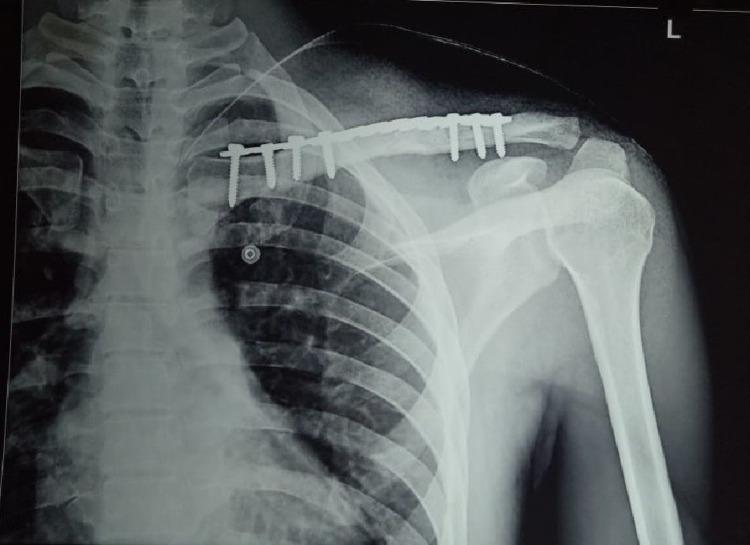

Introduction Fracture of the clavicle bone is a very common injury owing to its subcutaneous location. Controversy exists about the optimal treatment of midshaft clavicle fractures in the presence of significant displacement and comminution of the fracture. Traditionally, non-surgical management was considered the first treatment option for most clavicle fractures. However, recent evidence shows that the non-surgical option causes more complications than previously reported. The purpose of this study was to compare the clinical and radiological outcomes of conservative treatment and surgical treatment for midshaft clavicle fractures. Materials and methods A total of 45 patients meeting the inclusion criteria were included in this randomized study. The patients were allocated to two groups: conservative and operative on an alternate basis. Patients in the conservative group were managed with figure-of-eight bandage, whereas patients in the operative group were treated surgically by plate fixation. Primary outcome was recorded at six weeks, three months, six months, and 12 months follow-up using the Disabilities of the Arm, Shoulder, and Hand (DASH) and American Shoulder and Elbow Surgeons (ASES) scores. We also assessed patient's satisfaction after the treatment, fracture union, and complication rates among the study cohort. Results The ASES scores were significantly better in the operative group at three months and six months follow-up; however, at 12 months follow-up, there was no significant difference in the score between the groups. Although not statistically significant, the DASH score was better in the operative group than in the conservative group at all the follow-ups. This study showed that the time to union was lesser, rate of non-union was lower, and return to work was faster on the operative group. The mean satisfaction score in the operative and conservative groups was 4.16±0.76 and 4.05±1.24, respectively (p = 0.76). Conclusion This study suggests that open reduction and internal fixation with plate reduced the incidence of mal-union and non-union; however, surgical treatment showed no significant difference in the functional outcome as compared to conservative treatment.

材料与方法 本随机研究共纳入45例符合纳入标准的患者。患者被交替分配到两组:保守组和手术组。保守组患者采用“8”字绷带治疗,而手术组患者采用钢板固定手术治疗。在6周、3个月、6个月和12个月随访时,使用手臂、肩部和手部功能障碍(DASH)评分和美国肩肘外科医师(ASES)评分记录主要结局。我们还评估了研究队列中患者的治疗后满意度、骨折愈合情况和并发症发生率。

结果 在3个月和6个月随访时,手术组的ASES评分明显更好;然而,在12个月随访时,两组之间的评分没有显著差异。虽然无统计学意义,但在所有随访中,手术组的DASH评分均优于保守组。本研究表明,手术组的骨折愈合时间更短、不愈合率更低且恢复工作更快。手术组和保守组的平均满意度评分分别为4.16±0.76和4.05±1.24(p = 0.76)。

结论 本研究表明,钢板切开复位内固定降低了畸形愈合和不愈合的发生率;然而,与保守治疗相比,手术治疗在功能结局方面没有显著差异。